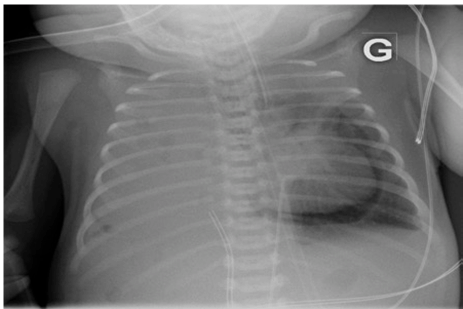

A five-day old girl presented with a pneumopericardium discovered fortuitously on a radiograph (Figure 1). She was born at term with a prenatal diagnosis of right-sided congenital diaphragmatic hernia (CDH) and required high frequency ventilation and inotrope/pressor therapy since birth. On day-6 the pneumopericardium increased and a pneumomediastinum was noted (Figure 2). The newborn remained stable without signs of cardiac tamponade. On day-7, the pneumopericardium/mediastinum resolved and a pneumoperitoneum appeared (Figure 3). The condition of the child improved at the same time and it was possible to gradually diminish ventilation pressures and discontinue inotrope/pressor therapy. No intestinal perforation was noted during surgery a few hours later.

Figure 2: X-ray at day-6. Pneumopericardium increased and apparition of pneumomediastinum.